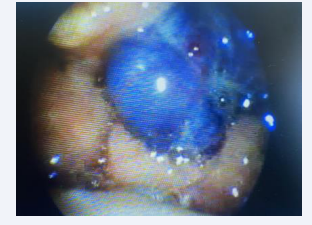

Nasopharyngolaryngeal fibroscopy revealed a multiple or single (to be clarified) tumor-like lesion with a vascular appearance and bluish coloration, non-pulsatile, and extensive. It occupied a significant volume in the supraglottic and left glottic region, at the level of Areas d’Avila I and II (Figures 1-3) [16,17].

Videolaryngoscopy capture image demonstrating laryngeal  hemangioma

Figure 1: Videolaryngoscopy capture image demonstrating laryngeal hemangioma

Videolaryngoscopy capture image demonstrating laryngeal  hemangioma with supraglottic extension

Figure 2 Videolaryngoscopy capture image demonstrating laryngeal hemangioma with supraglottic extension